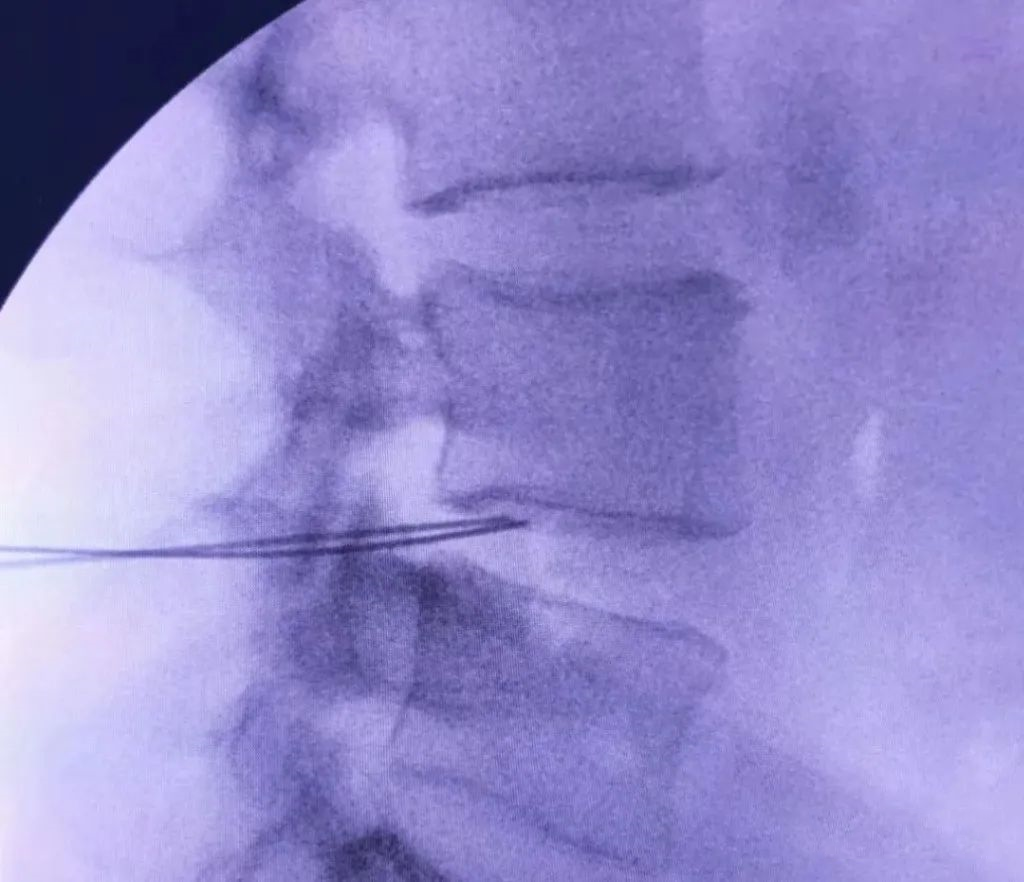

患者青年男性,以腰部疼痛为主诉入院。患者诉腰部疼痛,久坐及长时间行走时疼痛明显,平卧时疼痛减轻,夜间加重。患者腰椎CT未见明显腰椎间盘突出,但腰椎磁共振示L4-5椎间盘退变明显,诊断椎间盘源性腰痛。保守治疗只能缓解部分疼痛症状,不能解除引起腰痛的直接原因,可以进一步行腰椎间盘射频消融术治疗。

上图:腰椎磁共振示L4-5椎间盘突出不明显,但退变明显,行C臂X线引导下L4-5椎间盘双侧射频消融术

X线引导下L4-5椎间盘双侧射频针置入

正侧位示位置准确